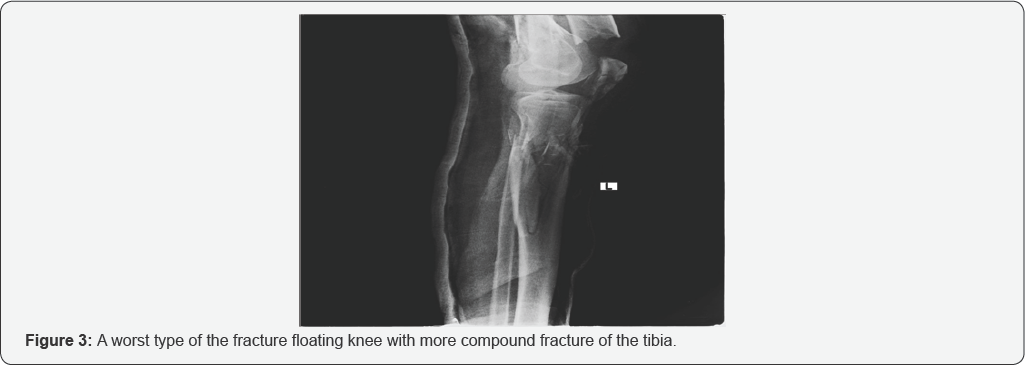

Male and female were 83.83% and 16.16% respectively 42.42% were found to have fractures while 57.57 were no fracture soft tissue injuries. Majority of fractures belonged to lower limb 25(59.52%) with 10(40%) Tibia, Fibula and 9(36%) knee joint while 17(40.47%) were associated to upper limb with top most 7(28%) carpel and metacarpal. All cases (100%) received analgesic medicines majority of them were given diclofenac sodium while a small proportion required opioid analgesic tramadol (Table 1) (Figures 1-3).